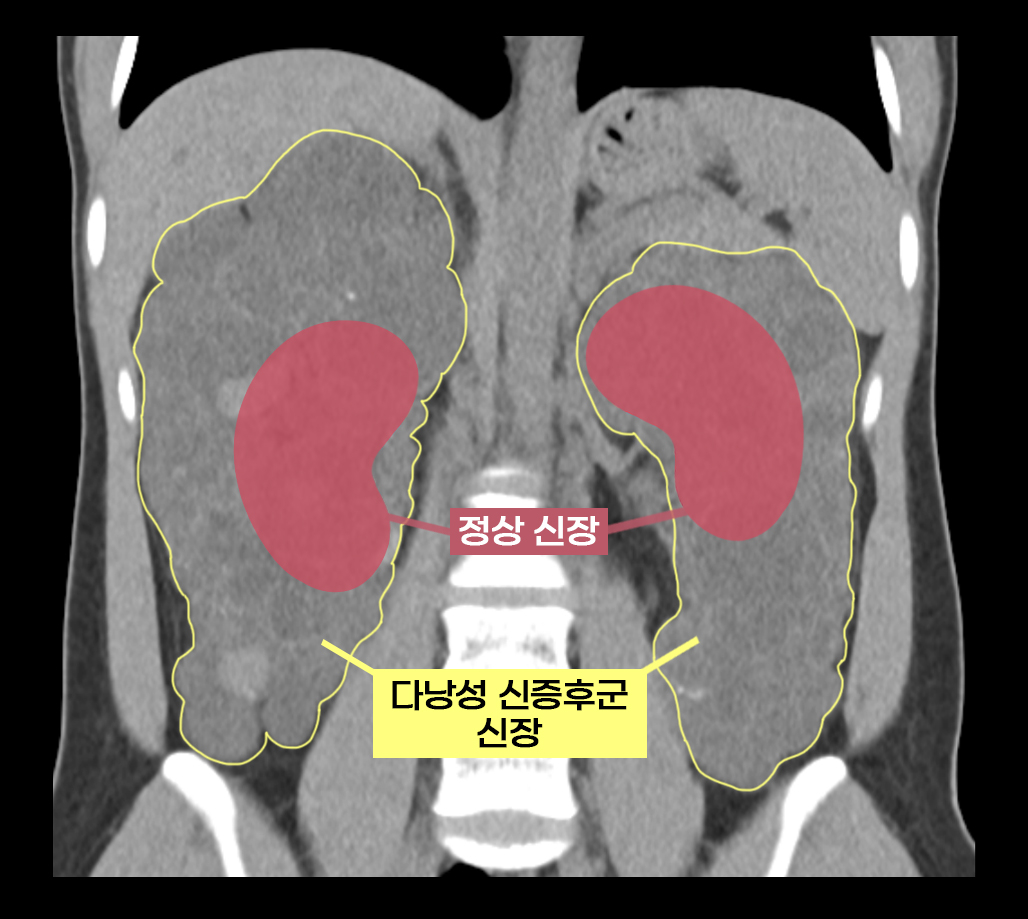

이 씨는 상염색체 우성 다낭성 신증후군을 앓았다. 다낭성 신증후군은 신장에 셀 수없이 많은 낭종이 발생해 원탑토토 최대 축구공만큼 커지는 유전 질환이다. 1,000명 중 한 명꼴로 비교적 흔하게 발생하며 대부분 만성 신부전으로 이어진다.

보통의 만성 신부전 환자는 원탑토토을 할 때 기존 신장을 그대로 두지만, 다낭성 신증후군 환자는 기존 신장을 떼어내야 한다. 이미 신장이 비대해진 상태이므로 새로운 신장이 들어올 공간을 확보해야 할 뿐만 아니라, 낭종 감염과 낭종 파열로 인한 출혈, 신장암 발병 등의 합병증 위험이 있어 양측 신장을 제거하고 원탑토토을 진행한다.